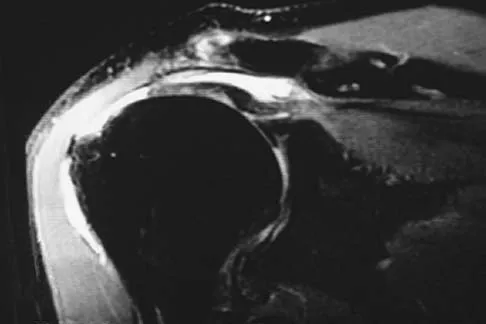

In patients older than age 40 years who sustain a first-time anterior dislocation of the shoulder, prolonged morbidity is most commonly associated with

In the study done by Pevny and associates, 35% of patients older than age 40 years sustained rotator cuff tears and 8% had axillary nerve palsies. All of the patients with axillary nerve palsy also had rotator cuff tears. Imaging of the rotator cuff is indicated in this age group. The incidence of recurrent instability in patients older than age 40 years is 10% to 15%. Pevny T, Hunter RE, Freeman JR: Primary traumatic anterior shoulder dislocation in patients 40 years of age and older. Arthroscopy 1998;14:289-294. Sonnabend DH: Treatment of primary anterior shoulder dislocation in patients older than 40 years of age: Conservative versus operative. Clin Orthop 1994;304:74-77.

Question 20High Yield

Explanation

Functional improvement after revision rotator cuff surgery is most likely to occur in patients with an intact deltoid, good-quality rotator cuff tissue, preoperative active elevation alone to 90 degrees, and only one prior rotator cuff repair. In this patient, the compromised deltoid origin might make functional improvement less likely. Djurasovic M, Marra G, Arroyo JS, et al: Revision rotator cuff repair: Factors influencing results. J Bone Joint Surg Am 2001;83:1849-1855. Bigliani LU, Cordasco FA, McIlveen SJ, et al: Operative treatment of failed repairs of the rotator cuff. J Bone Joint Surg Am 1992;74:1505-1515.